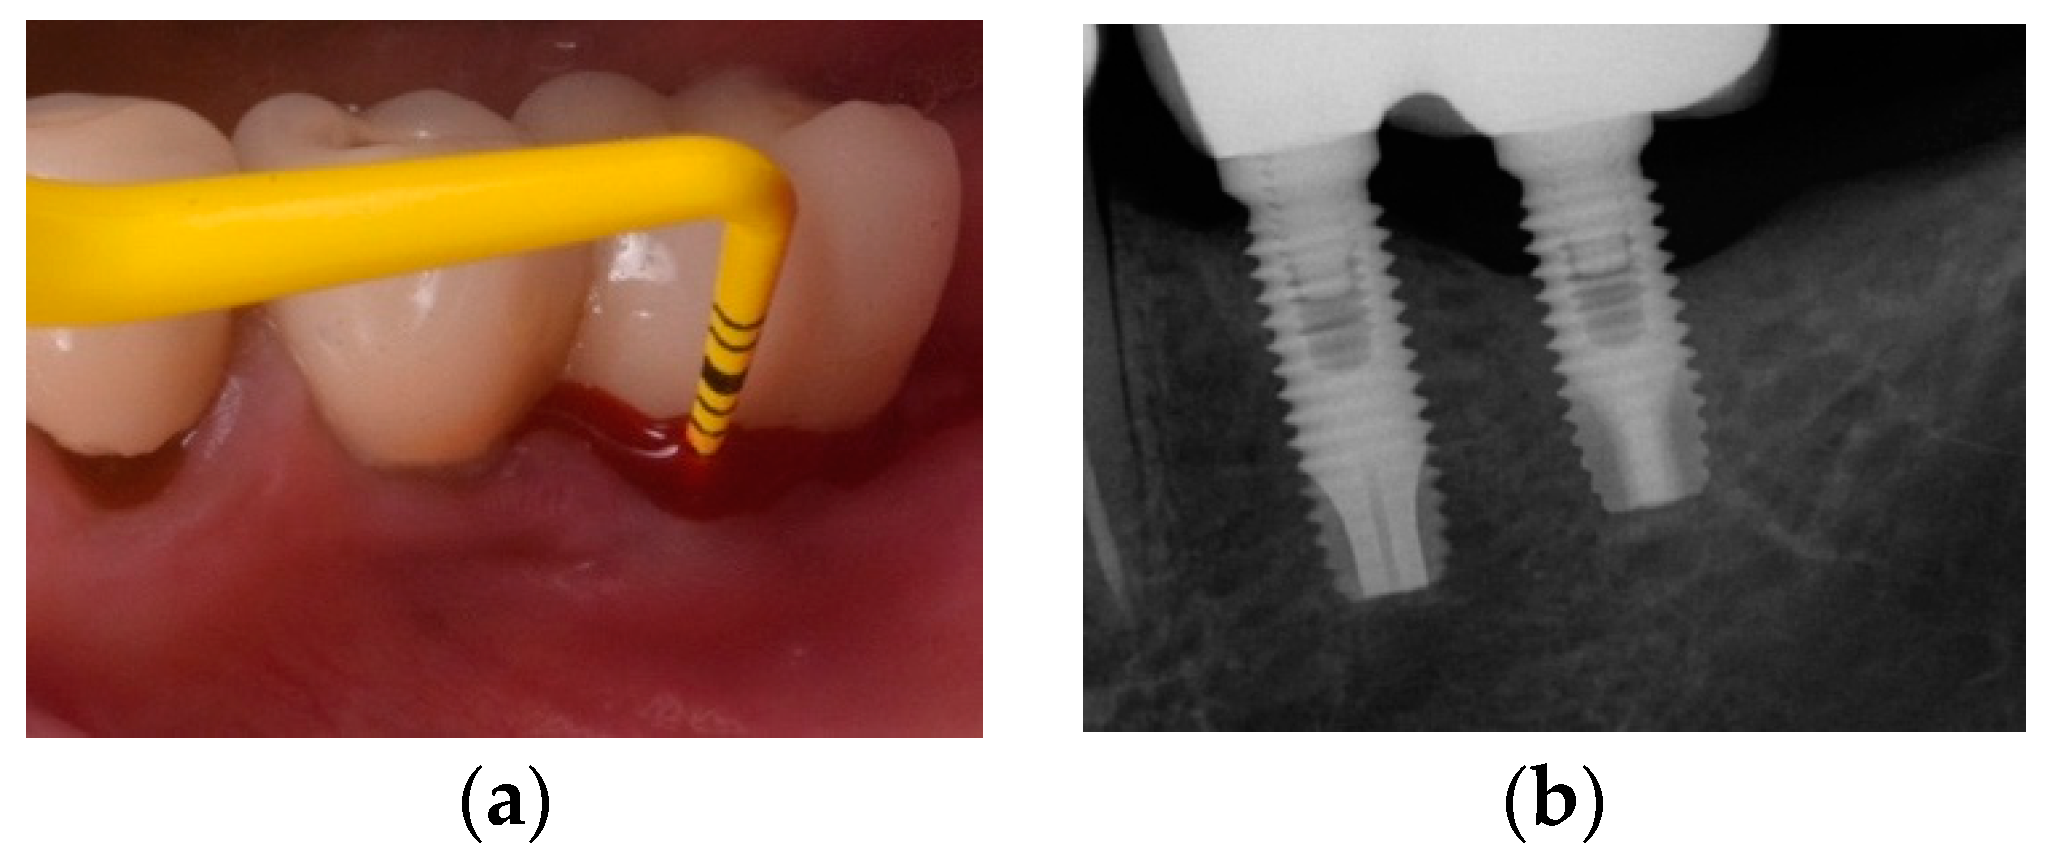

- Monje, A.; Blasi, G. Significance of keratinized mucosa/gingiva on peri-implant and adjacent periodontal conditions in erratic maintenance compliers. J. Periodontol. 2019, 5, 445–453. [Google Scholar] [CrossRef] [PubMed]

- Roccuzzo, M.; Grasso, G.; Dalmasso, P. Keratinized mucosa around implants in partially edentulous posterior mandible: 10-year results of a prospective comparative study. Clin. Oral. Implant Res. 2016, 4, 491–496. [Google Scholar] [CrossRef] [PubMed]

- Ravidà, A.; Saleh, I.; Siqueira, R.; Garaicoa-Pazmiño, C.; Saleh, M.H.A.; Monje, A.; Wang, H.L. Influence of keratinized mucosa on the surgical therapeutical outcomes of peri-implantitis. J. Clin. Periodontol. 2020, 4, 529–539. [Google Scholar] [CrossRef] [PubMed]